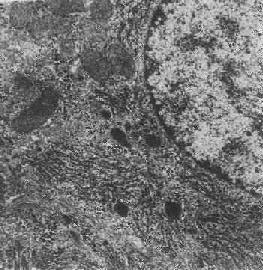

图1-13 初级溶酶体

图中央及中下方之卵圆形电子致密小体,外围单层包膜。(图中及下部片层状膜性结构为粗面内质网(正常肝细胞)